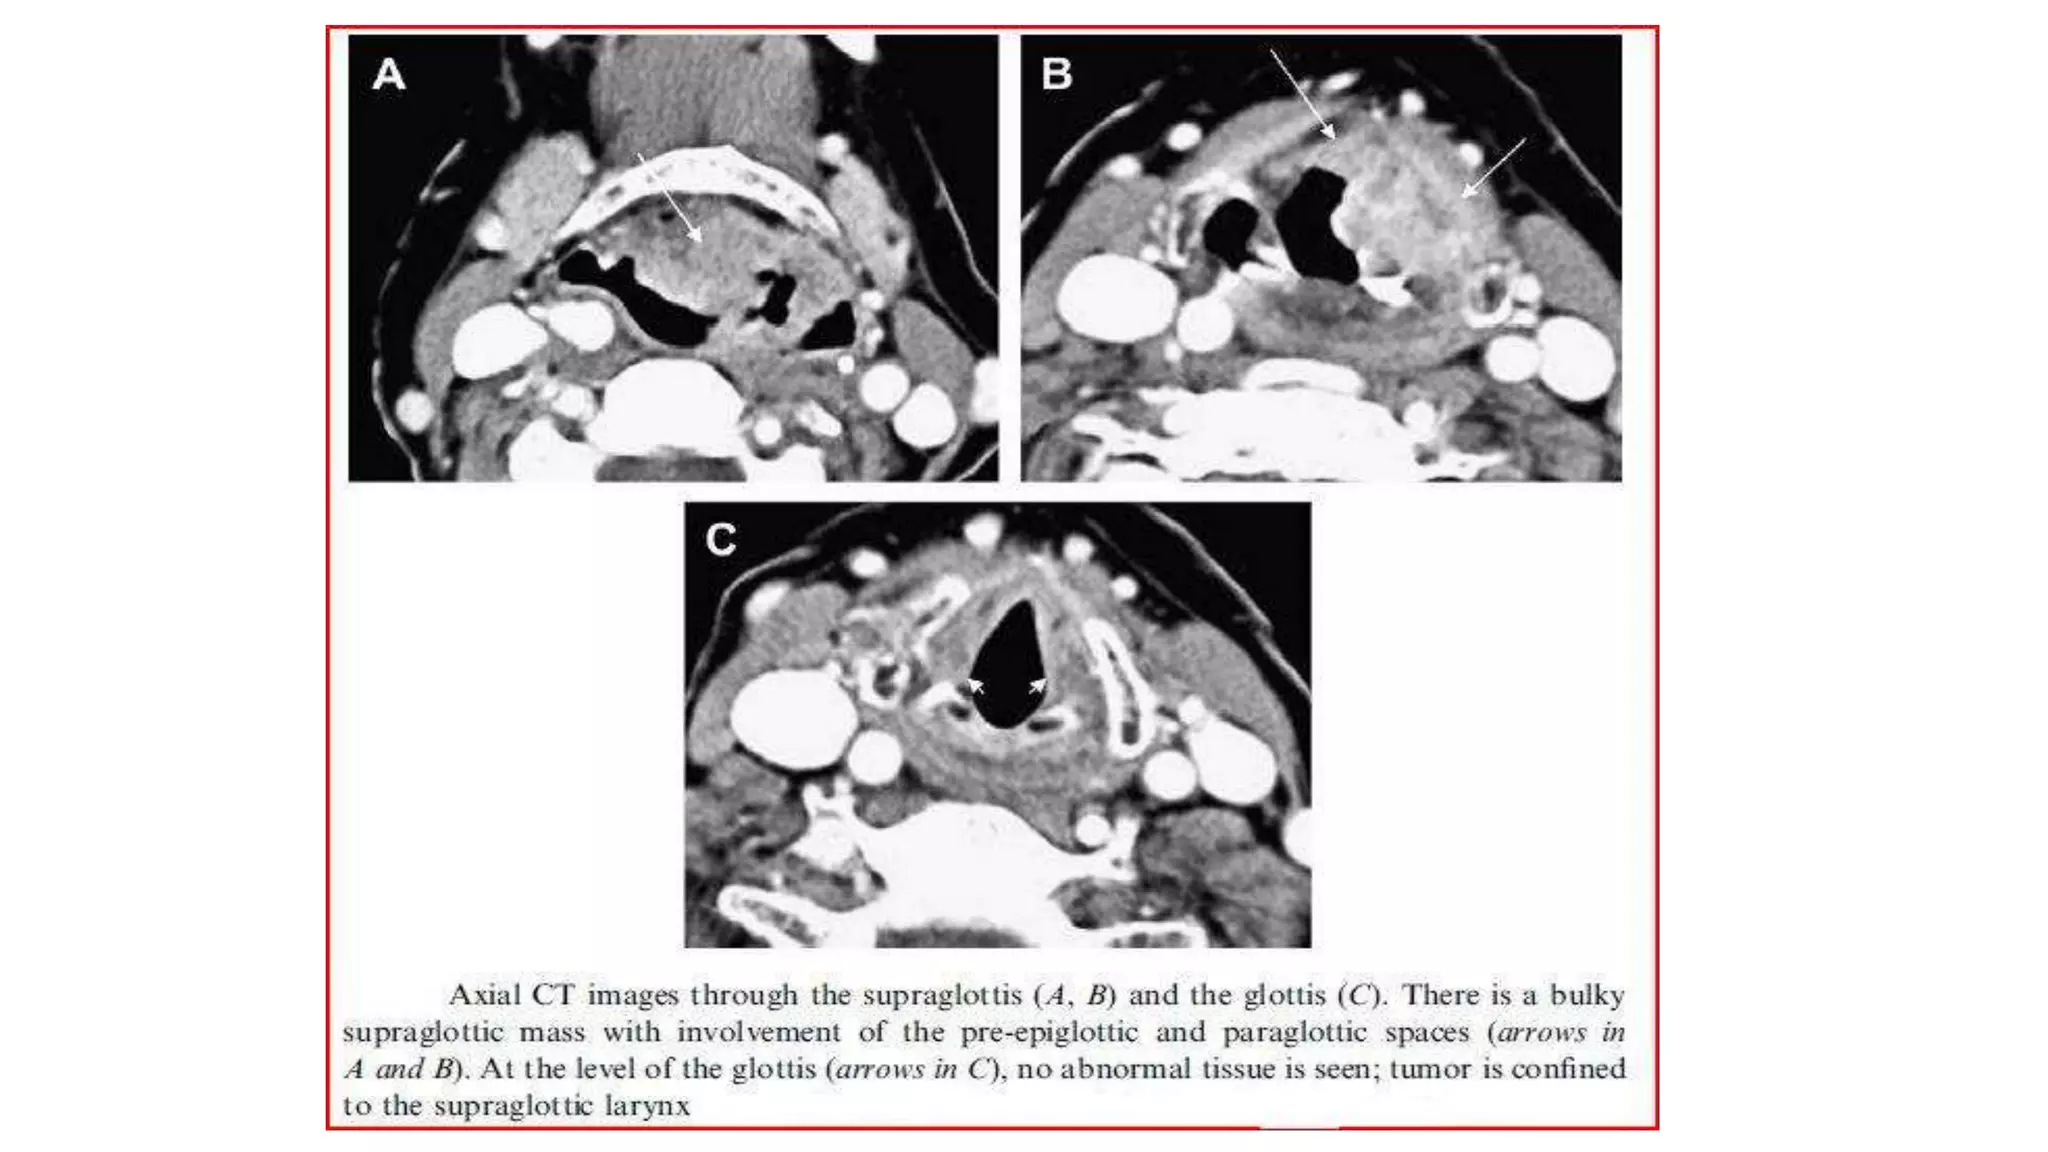

CARCINOMA HYPOPHARYNX • abnormalenhancing mass centred upon the right larynx/hypopharynx with large cervical lymph node • superior extent of the lesion extends from the right aryepiglottic fold, involving the paraglottic right space (without crossing the midline) and extending into the supraglottic larynx. • Inferior extent extends to right true cord with likely subglottic spread.